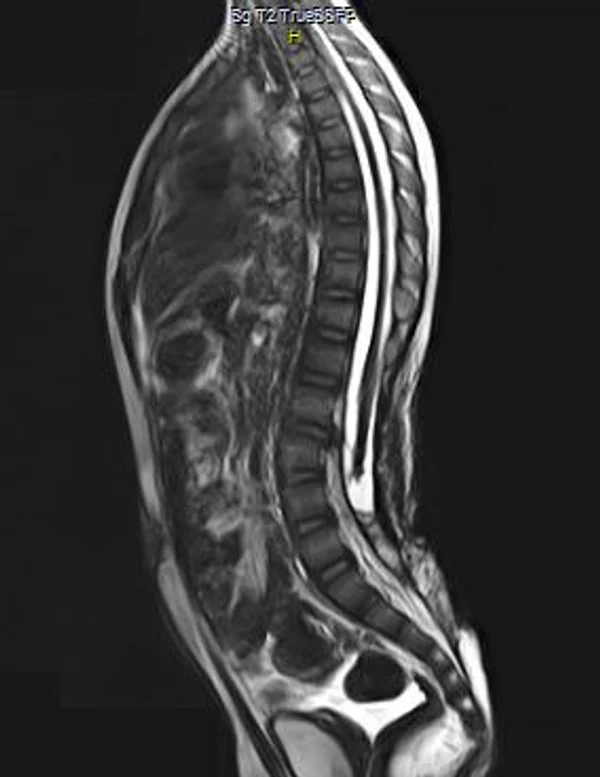

Spina bifida, спинно-мозговые грыжи, диастематомиелия, липоменингомиелолоцеле, фиксированный спинной мозгSpina bifida включают различные типы нарушения закладки и развития нервной трубки на спинальном уровне, что сопровождается незаращением дужек позвоночника и часто сопровождается одновременным пороком развития спинного мозга и его оболочек. Встречаются у 1 на 1000 – 3000 новорожденных. Могут наблюдаться в различных отделах позвоночника, но наиболее часто встречается в пояснично-крестцовом отделе. Незаращение дужек позвонков с наличием грыжевого выпячивания обозначается в литературе по разному: спинно-мозговые грыжи, spina bifida, spina bifida cystica, spina bifida vera, spina bifida typica, spina bifida aperta. Классификация spina bifida aperta: I Рахишизис. II Спинномозговые грыжи. Менингоцеле. Менингорадикулоцеле. Миеломенингоцеле. Миелоцистоцеле. Липоменингомиелоцеле. Основные сопутствующие пороки центральной нервной системы: Гидроцефалия до 65-85%. Аномалия Киари 2. Сирингомиелия.